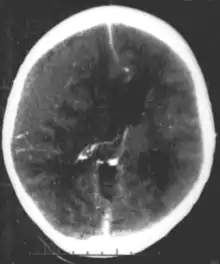

A number of infectious diseases can be transmitted congenitally (either before or at birth), and can cause serious neurodevelopmental problems, as for example the viruses HSV, CMV, rubella (congenital rubella syndrome), Zika virus, or bacteria like Treponema pallidum in congenital syphilis, which may progress to neurosyphilis if it remains untreated. Protozoa like Plasmodium[22] or Toxoplasma which can cause congenital toxoplasmosis with multiple cysts in the brain and other organs, leading to a variety of neurological deficits.